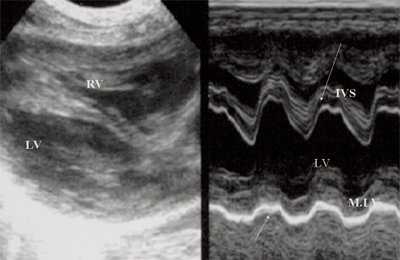

Нагрузка сопротивлением возникает при ситуации, когда выброс крови из желудочков сердца в магистральные сосуды затруднен на уровне полулунных клапанов (стеноз аорты и легочной артерии), подклапанного пространства (идиопатический гипертрофический субаортальный стеноз, подклапанный стеноз аорты или легочной артерии), на протяжении сосудистого русла (коарктация аорты) либо при значительном увеличении выходного сопротивления (синдром Эйзенменгера). В результате затруднения выброса крови резко возрастает напряжение миокарда соответствующего желудочка при относительно стабильном объеме крови, что служит проявлением систолической перегрузки сердца. При систолической перегрузке желудочков сердца независимо от нозологической формы порока полость желудочка, несущего основную нагрузку сопротивлением, умеренно увеличивается в размерах. В ответ на нагрузку сопротивлением на эхокардиограмме выявляется гипертрофия миокарда соответствующего желудочка, и чем больше сопротивление выбросу, тем резче выражена степень гипертрофии миокарда соответствующего желудочка и межжелудочковой перегородки (рис. 1) [3].

Рис. 1. Систолическая перегрузка правого желудочка. Поперечное сечение желудочков сердца при стенозе легочной артерии. Градиент давления правый желудочек - легочная артерия равен 200 мм рт.ст. Выраженная гипертрофия межжелудочковой перегородки и миокарда передней стенки правого желудочка.

Характерными особенностями выраженной объемной перегрузки правого желудочка являются дилатация желудочка, при которой толщина миокарда не превышает верхней границы нормы, увеличение правого предсердия, парадоксальный характер движения межжелудочковой перегородки и увеличение амплитуды движения трикуспидального клапана (рис. 2, 3).

Рис. 2. Длинная ось сердца. Объемная перегрузка правого желудочка при дефекте межпредсердной перегородки. Объем сброса крови превышает 200% МОС. Отмечается выраженная дилатация правого желудочка.

Рис. 3. Объемная перегрузка правого желудочка при дефекте межпредсердной перегородки. В- и М-сканирование. Стрелкой показан парадоксальный характер движения межжелудочковой перегородки.

Для левого желудочка признаком объемной перегрузки являются увеличение полости левого предсердия и желудочка, а также экскурсии межжелудочковой перегородки и миокарда задней стенки левого желудочка (рис. 4).

Рис. 4. Объемная перегрузка левых отделов сердца. В- и М-сканирование. Отмечается усиление экскурсии межжелудочковой перегородки и миокарда задней стенки левого желудочка.

IVS - межжелудочковая перегородка, MLV - миокард левого желудочка, LV и RV - левый и правый желудочек.